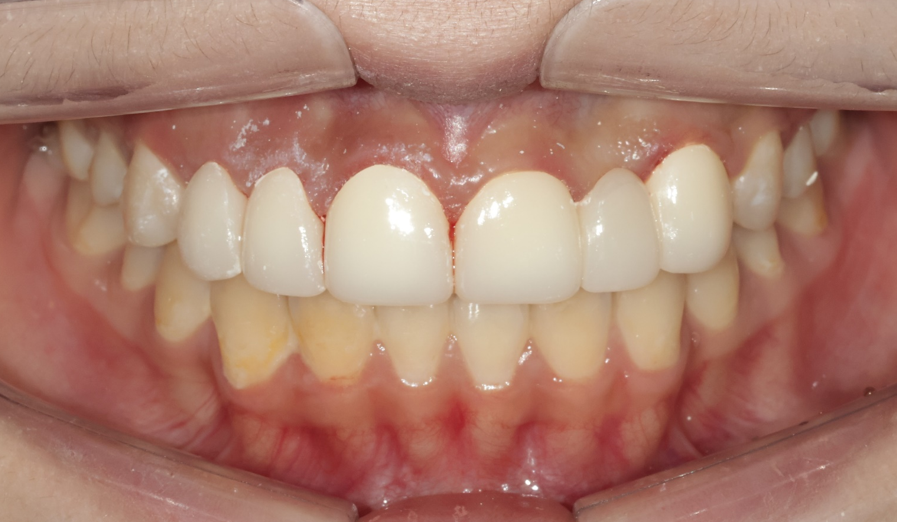

4단계: 최종 보철물 세팅 – 완성된 미소

임시치아 단계에서 확인된 형태를 바탕으로 최종 보철물을 제작했습니다. 최종적으로 좌우 대칭성, 치아 간 비율, 잇몸 라인의 조화가 모두 달성되었습니다. 그리고 무엇보다 기쁜 점은, 모든 치아의 신경을 살린 채 (생활치 상태로) 치료를 완료했다는 것입니다. 꼭 필요한 부분만 최소한으로 삭제하여 신경치료 없이 마무리할 수 있었습니다.

최종 보철물이 세팅된 모습 – 자연스럽고 조화로운 미소가 완성되었습니다

Before & After – 치료 전후 비교

치료 전과 후를 비교해보면, 그 변화가 확연히 드러납니다.

| 치료 전 (Before) | 치료 후 (After) | |

|---|---|---|

| 치아 형태 | 왜소치, 잔존유치, 결손 존재 | 자연스럽고 균일한 치아 형태 |

| 잇몸 라인 | 좌우 비대칭, 불규칙 | 좌우 대칭, 조화로운 라인 |

| 치아 비율 | 앞니가 상대적으로 크고 부조화 | 전체적으로 조화로운 비율 |

| 전체적 인상 | 불규칙하고 비심미적 | 자연스럽고 아름다운 미소 |

교정 + 잇몸성형 + 심미보철이라는 종합적 접근이 만들어낸 결과입니다. 환자분도 치료 결과에 매우 만족해하셨습니다.